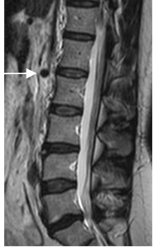

Fig 23. Cono medular.

A: RM sagital en T2. Cono medular normal, entre L1 y L2.

B: RM axial en T2. Como medular normal, con apariencia de araña.